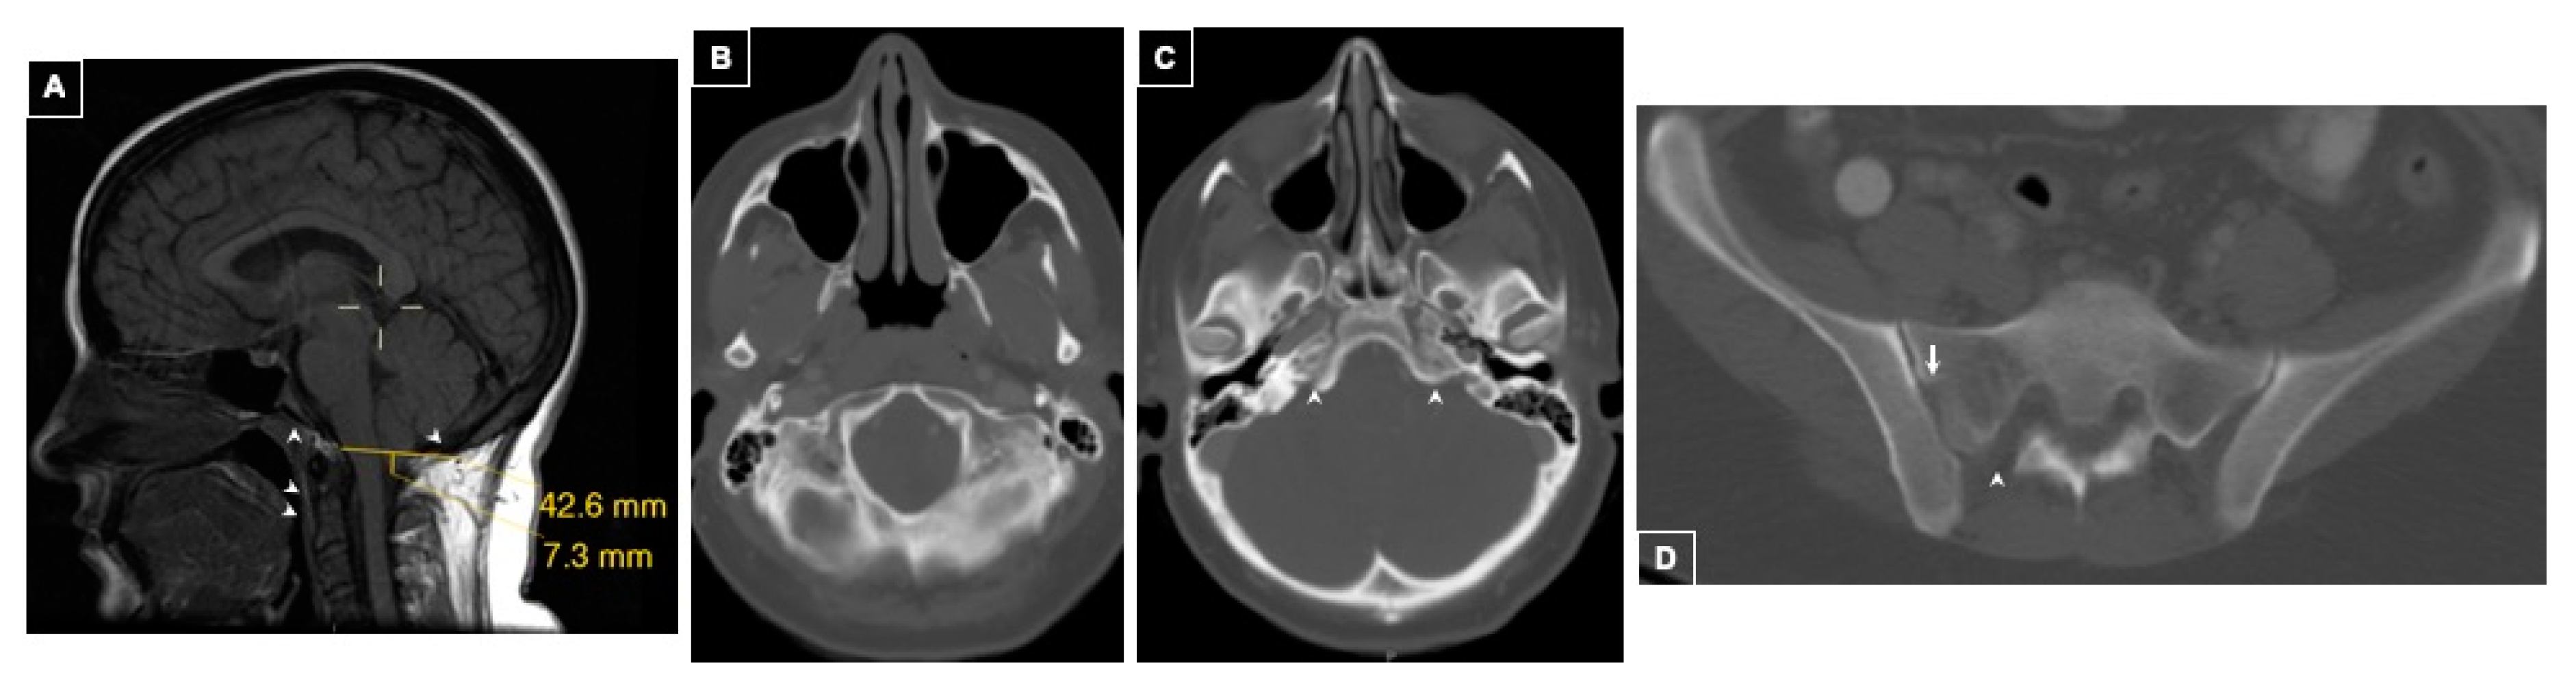

Imaging Findings

| Chiari Malformation Features | ||

| Lowest Cerebellar Tonsillar Position (mm) | 7 | 8 |

| Position of Right Cerebellar Tonsil (mm) | 4 | 6 |

| Position of Left Cerebellar Tonsil (mm) | 7 | 8 |

| Shape of Cerebellar Tonsils | Pegged | Round |

| Ventral CSF Space (12 ± 2.3 mm) [8] | 4 | 9 |

| Dorsal CSF Space (19 ± 2.3 mm) [8] | 0 | 2 |

| Pontomedullary Junction to Foramen Magnum (19 ± 3 mm) [10] | 14 | 15 |

| Supraoccipital Bone Length (41 ± 5 mm) [10] | 35 | 46 |

| Clival Length (43.4 ± 4.4 mm) [10] | 41 | 44 |

| Tentorial Angle (27–52°) [10] | 50.40 | 63.07 |

| Klaus Index Height (38.0 ± 5 mm) [10] | 49 | 51 |

| Boogaard Angle (133.8 ± 6.5°) [10] | 130 | 114 |

| McGregor Line (<4.5 mm) | <0 | <0 |

| Posterior Fossa Height (32 ± 3 mm) [10] | 32 | 39 |

| Uncalcified Petroclival Synchondrosis | Yes | Yes |

| Sacral spina bifida occulta | Yes | Yes |